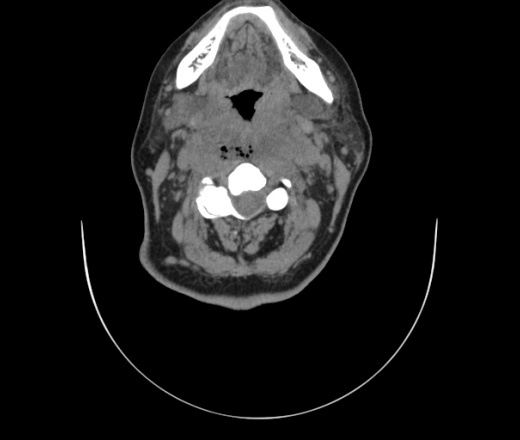

Женщина поступила в х/о спустя 4 дня после того как при употреблении карася подавилась костью.

Наличие газа в средостении на протяжении тел С2-С6 (медиастинальна эмфизема); рыбная кость на уровне тела С6.

При всем уважении, но говорить о медиастинальной эмфиземе, оценивая мягкие ткани шеи, как-то слишком резко. На мой взгляд, это ретрофарингеальное пространство.

Согласен с Вами; конечно, наличие газа в клетчатке ретрофарингеального пространства (затмение с опечаткой..). К сожалению, процесс "продвигается" к медиастиниту. Но почему никто, не отмечает наличие рыб. кости; или это для Всех очевидно?

Так вы уже отметили. Хотя ориентировал бы не скелетотопически, а на перстнечерпаловидный сустав.

Кость то мы сразу выявили, размеры где то 17*2мм, но ее так и не получается найти в этой каше